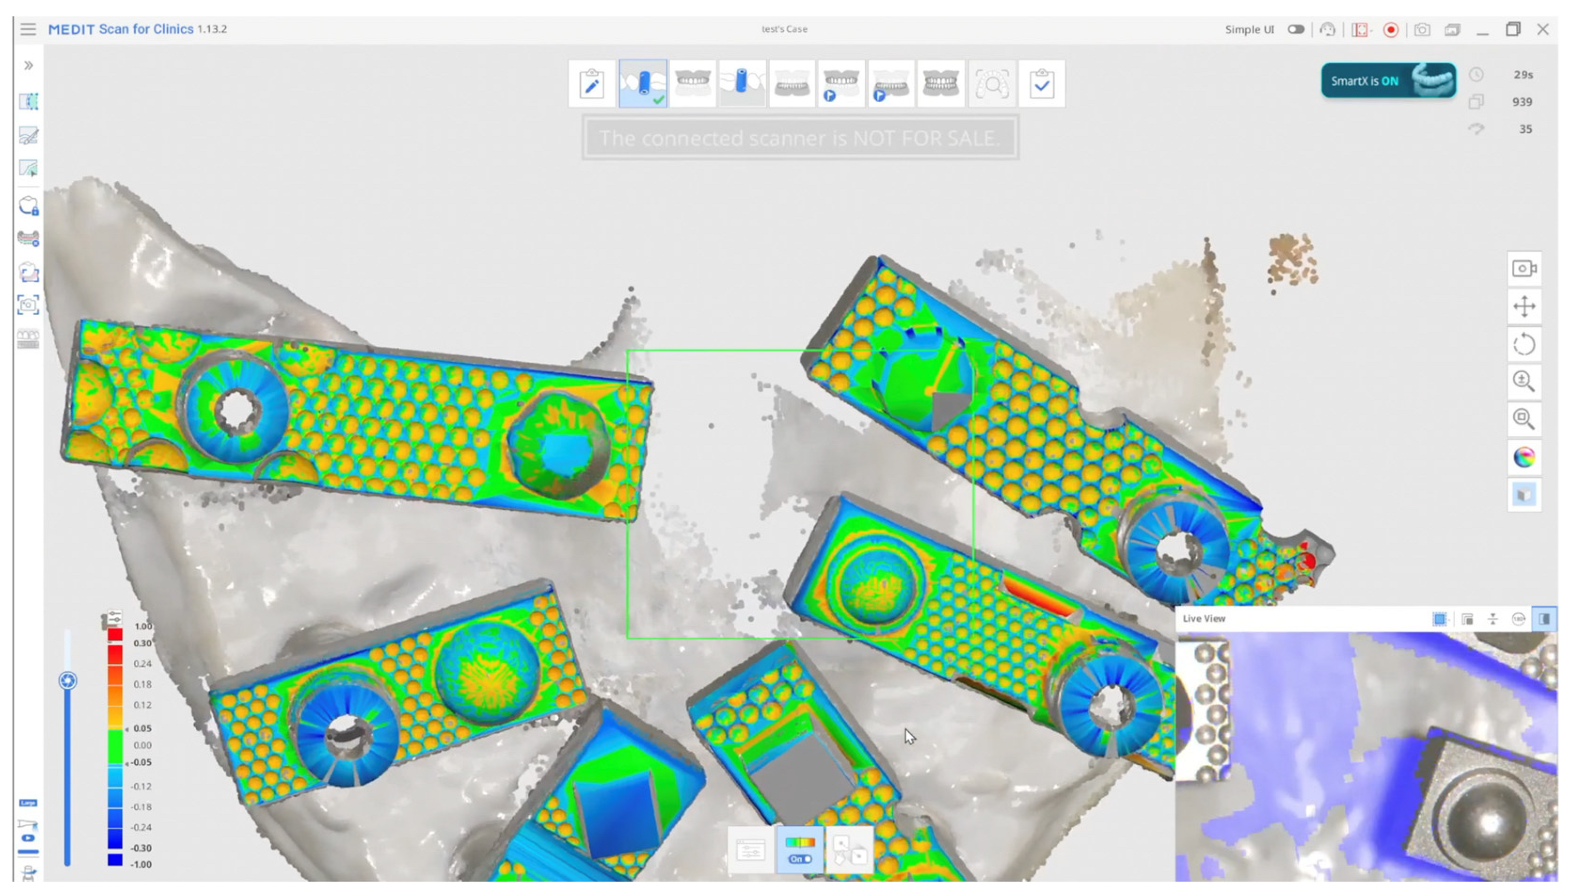

2. Materials and Methods

2.3. Scanning Procedure

Scanners in the Study